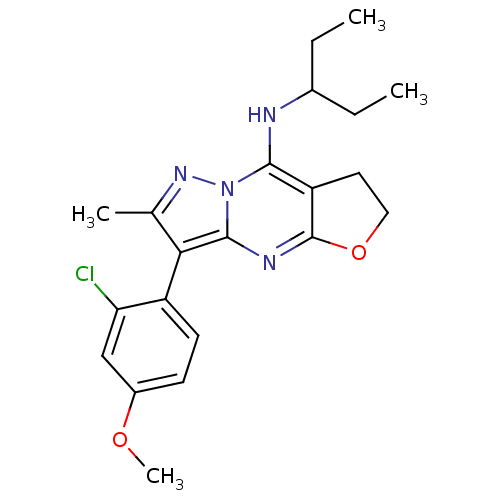

TargetCorticotropin-releasing factor receptor 1(Homo sapiens (Human))

Dupont Pharmaceuticals

Curated by ChEMBL

Dupont Pharmaceuticals

Curated by ChEMBL

Affinity DataEC50: 0.700nMAssay Description:Antagonist activity at human CRF1 receptor expressed in CHO-K1 cells assessed as inhibition of CRF-induced cAMP accumulation after 15 mins by cAMP en...More data for this Ligand-Target Pair